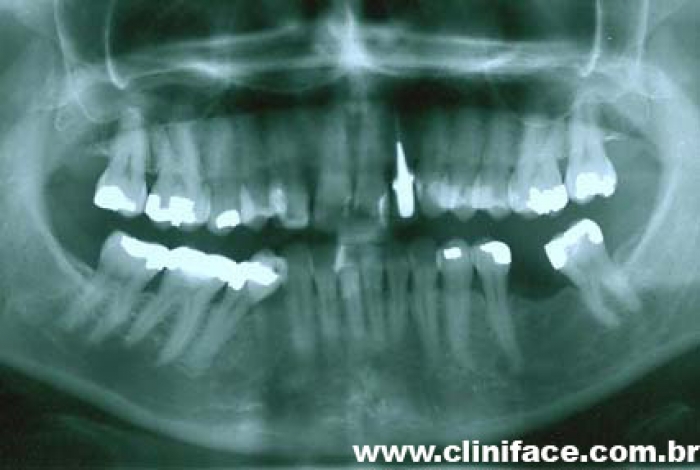

Imagem inicial e final de caso de agenesia dental, reabilitado com implante unitário no elemento 12

Raio X mostrando agenesia do elemento 12, reabilitado com implante e prótese fixa em porcelana